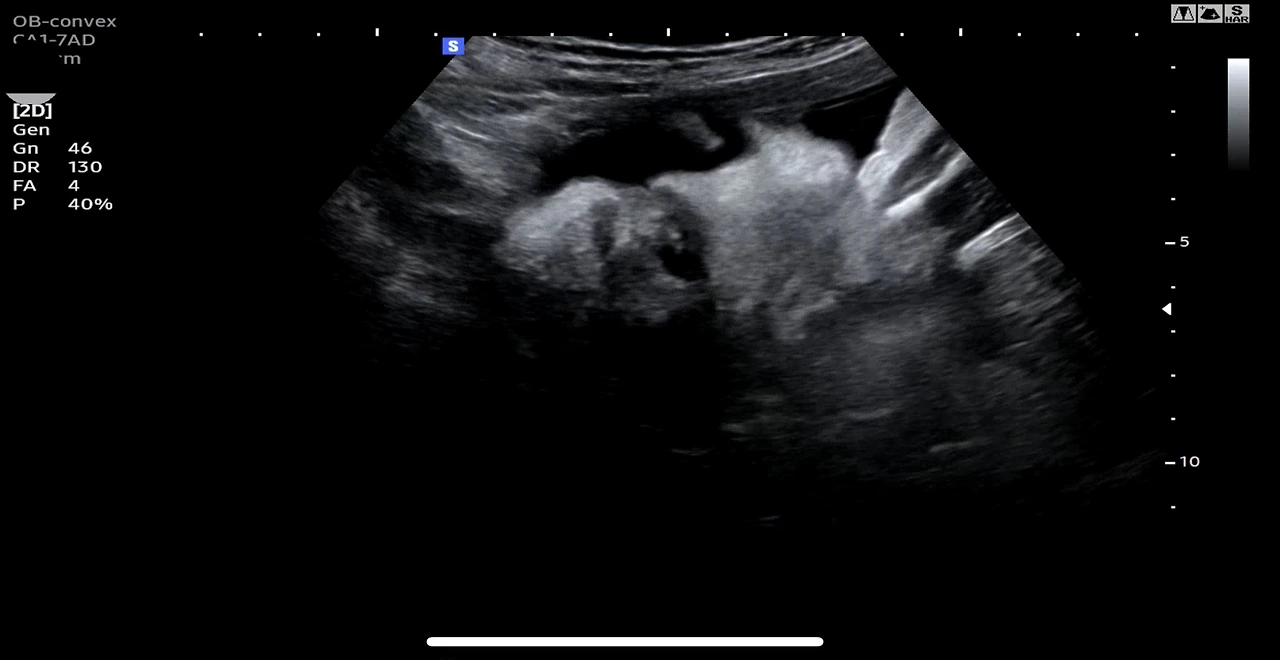

그건 바로 태아 초음파 사진이었다. "세상에나!"

3달 만에 임신이 되어서, 오늘 병원에 가서 확실하게 확인하고 오는 길이란다.써 5주째라니...! 이보다 더 큰 기쁨과 이보다 더 좋은 생일선물이 또 있을까?